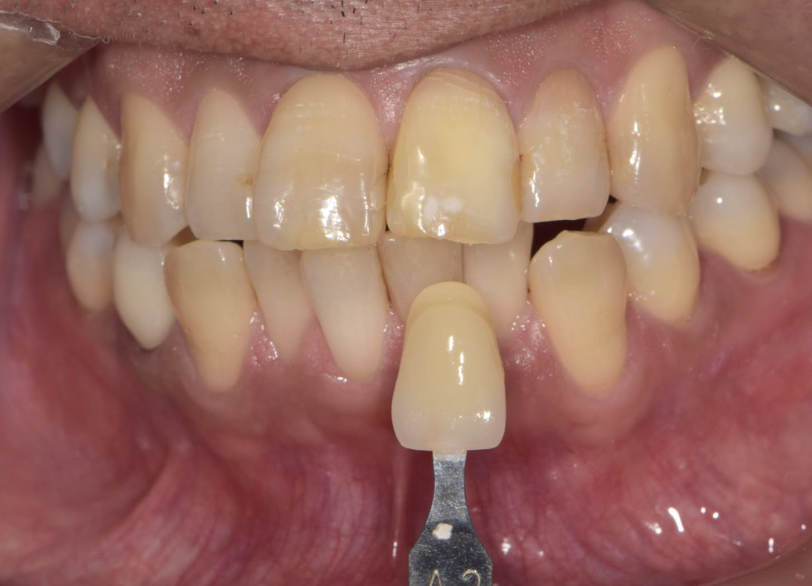

ホワイトニング

| 診断 | 失活による歯の黒色変化 | ||

| 処置内容 (または主訴) | 失活歯に対するウオーキングブリーチ | ||